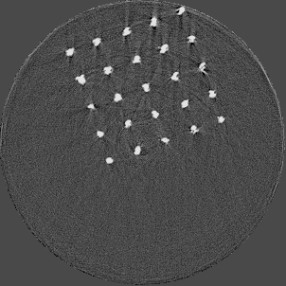

For the beam hardening study, we used Medipix All Resolution System (MARS) [12] containing a Medipix3RX ASIC with a 2 mm CdTe sensor bump bonded at 110 m in a single chip layout. All the acquisitions in this paper were carried out in CSM. The detector assembly is a module of the MARS camera which also contains a readout board, peltier cooling system and an integrated bias-voltage board. A negative bias voltage of -440 V was applied across the sensor during the acquisitions. The MARS scanner system comprises of MARS camera, a rotating internal gantry and an 80 kVp Source-Ray SB-80-1K x-ray tube (Source-Ray Inc, Ronkonkoma, NY) with a tungsten anode having 1.8 mm aluminium (Al) equivalent intrinsic filtration. The focal spot size is approximately 33 m [13]. Mechanical motor control (gantry rotation, source to detector translation, camera translation and sample translation), detector energy response calibration and threshold equalization were performed using the custom built MARS scanner software. The samples used in this study are shown in figure 2 and its description is provided in table 1.

Figure 7 shows a single slice spectral reconstruction of the Mg scaffold. Due to low atomic number of Mg (Z = 12) compared to Ti (Z = 22), the results did not exhibit any significant beam hardening effects. Low energy reconstruction shows good spatial information while high energy ranges are limited by photon noise. In scans involving smaller samples made from low-Z materials like Al or Mg, acquiring low energy quanta in CSM provide high spatial information with minimum or no beam hardening effects. Figure 8 illustrates a single slice spectral reconstruction of the Ti mesh. Similar to the Ti scaffold, streaks are less pronounced in the mid and high energy ranges.